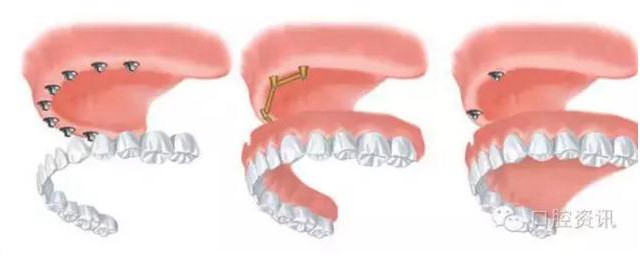

1 . 種植牙

種植牙可以替代單顆,多顆或者全口牙齒。與常規(guī)義齒相比種植牙具

有以下優(yōu)點:1.支持,固位和穩(wěn)定功能較好;2.避免了打磨天然牙引

起的牙體組織損傷;3.舒適度較好。

4.jpg

圖4. 在前牙區(qū)使用種植體支撐牙冠來替代單顆牙齒

5.jpg

圖5. 在后牙區(qū)使用種植體支撐橋體替代多顆牙齒

6.jpg

圖6. 全口牙齒缺失種植治療的各種選擇((1) 固定式(2) 桿卡式可摘義齒(3)球帽式可摘義齒)